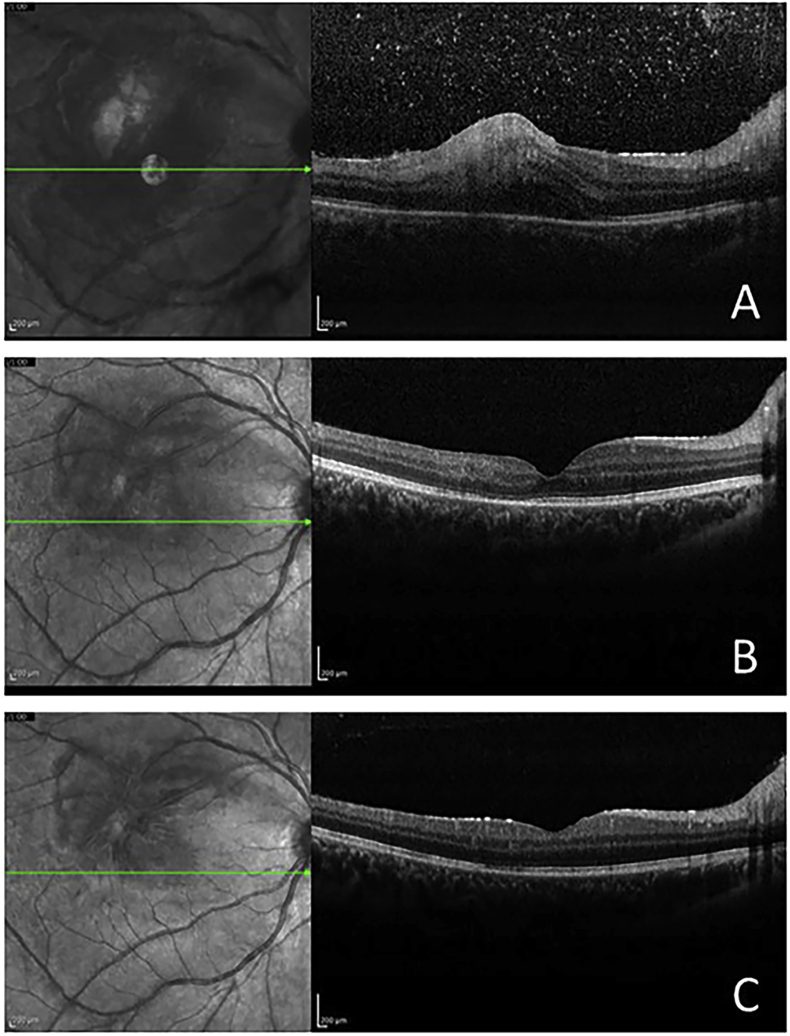

Fig. 2.

SD-OCT of the right eye. A. Upon presentation, revealing vitreous cells, increased reflectivity from the inner retinal layer, retinal thickening, and choroidal shadowing. B Four weeks after presentation, showing resolution of vitreous cells, along with substantial improvement of nerve fiber layer and retinal thickness. C. Upon completion of a 6-week course of therapy, there is normalization of retinal thickness and total resolution of the edema.

At the four-week follow-up visit, her visual acuity had improved to 20/25 OD, the IOP normalized, and resolution of the vitritis was noted. The right fundus exam revealed significant improvement of the retinitis along with mild Kyrieleis’ vasculitis and perivenular sheathing (Fig. 1B), while the SD-OCT revealed substantial improvement of the nerve fiber layer and intraretinal thickening (Fig. 2B). Upon completion of a six weeks course of therapy, the patient recovered her baseline visual acuity of 20/20 on both eyes, the right fundus exam revealed resolution of the retinal vasculitis, along with residual parafoveal chorioretinal scarring superotemporally (Fig. 1C). SD-OCT of the right macula showed normalization of macular thickness and total resolution of the edema (Fig. 2C).